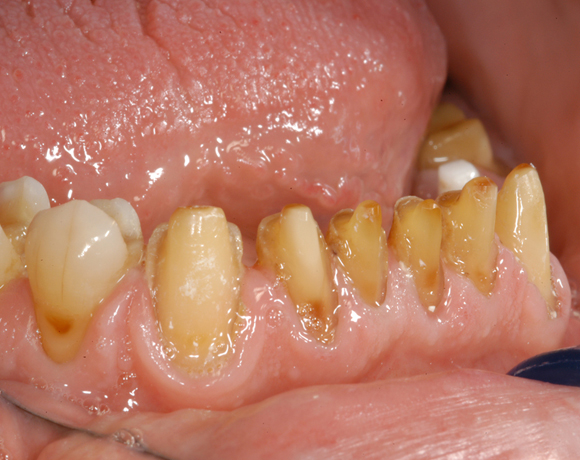

Im vorliegenden Patientenfall waren die Zähne 11 – 26 mit einer provisorischen Brücke versorgt, der Patient konnte damit aber nicht essen. Auch im Unterkiefer waren die vorhandenen Kronen und Brücken insuffizient. Es wurde eine komplette Neuversorgung für Ober- wie Unterkiefer geplant.